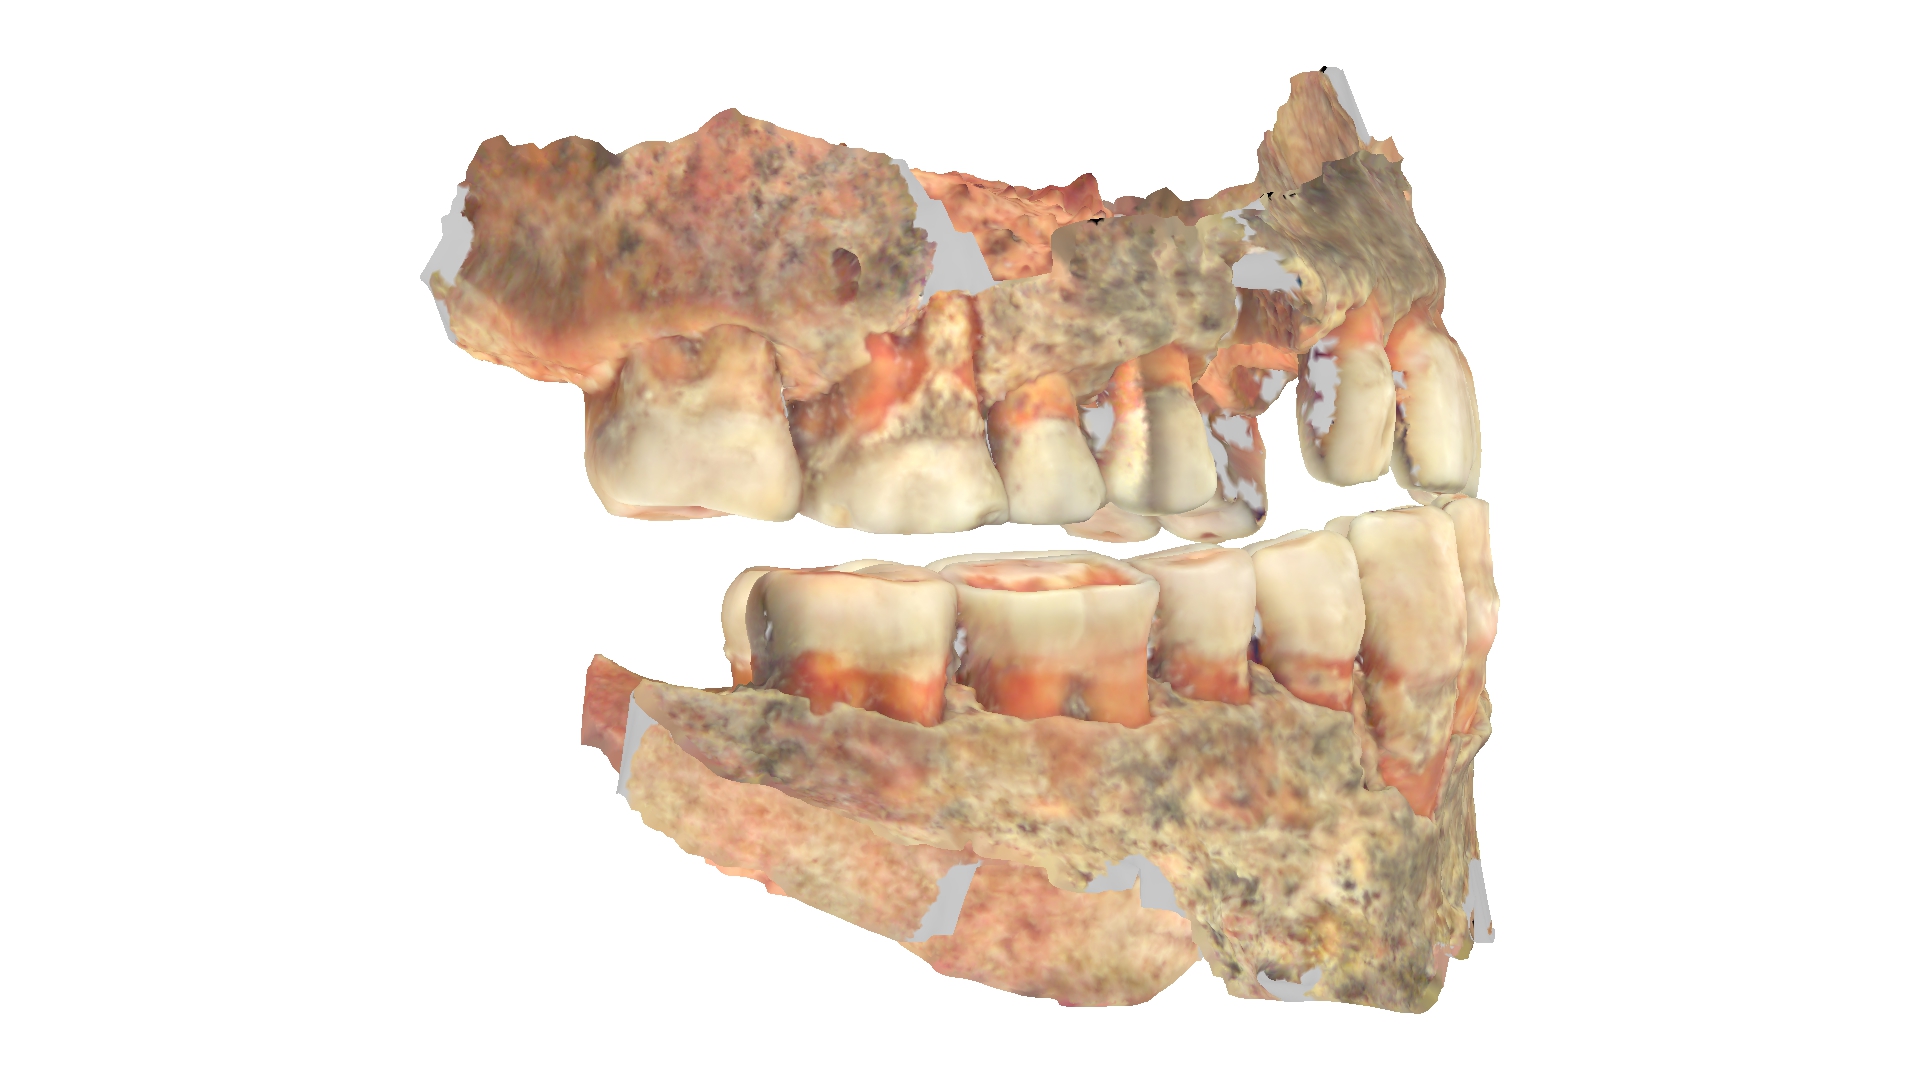

Zęby w 3D

Cyfrowe skany 3D też dostarczyły wielu ciekawych informacji, bo okazuje się, że przynajmniej jeden aspekt zdrowia zębów raczej nie przysparzał im zmartwień – zgryz.

– Raczej nie musieli chodzić do ortodonty. W tych przypadkach, w których mieliśmy taką możliwość, czyli były zachowane szczęka i żuchwa, stwierdzaliśmy prawidłowe warunki zgryzowe (zgryz eugnatyczny). To również może być zasługą diety. Żucie i gryzienie twardych, włóknistych produktów sprzyja prawidłowemu rozwojowi kości szczęki oraz żuchwy, a tym samym właściwemu ustawieniu się zębów. Nie bez znaczenia może być też fakt braku smoczków dla dzieci, które – zbyt długo używane – sprzyjają wadom zgryzu. Dzieci wtedy karmiono piersią, a dieta nie zawierała aż tylu miękkich, papkowatych produktów – zauważa ekspertka.

Jeden z pacjentów miał szpary między zębami zwane fachowo tremami. Taki odstęp tylko między jedynkami nazywa się diastemą.